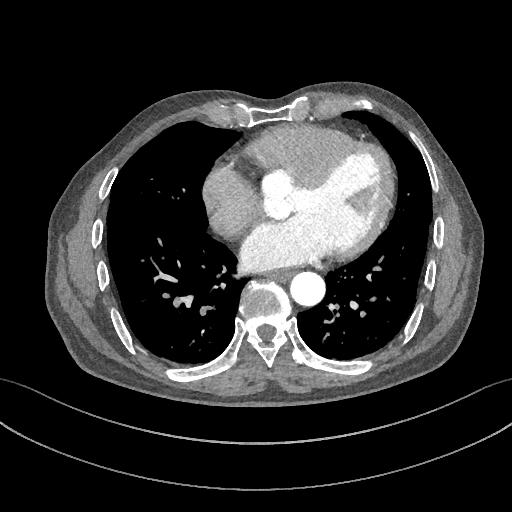

增强CT一看,吓到一大片!太惊悚了!

图6